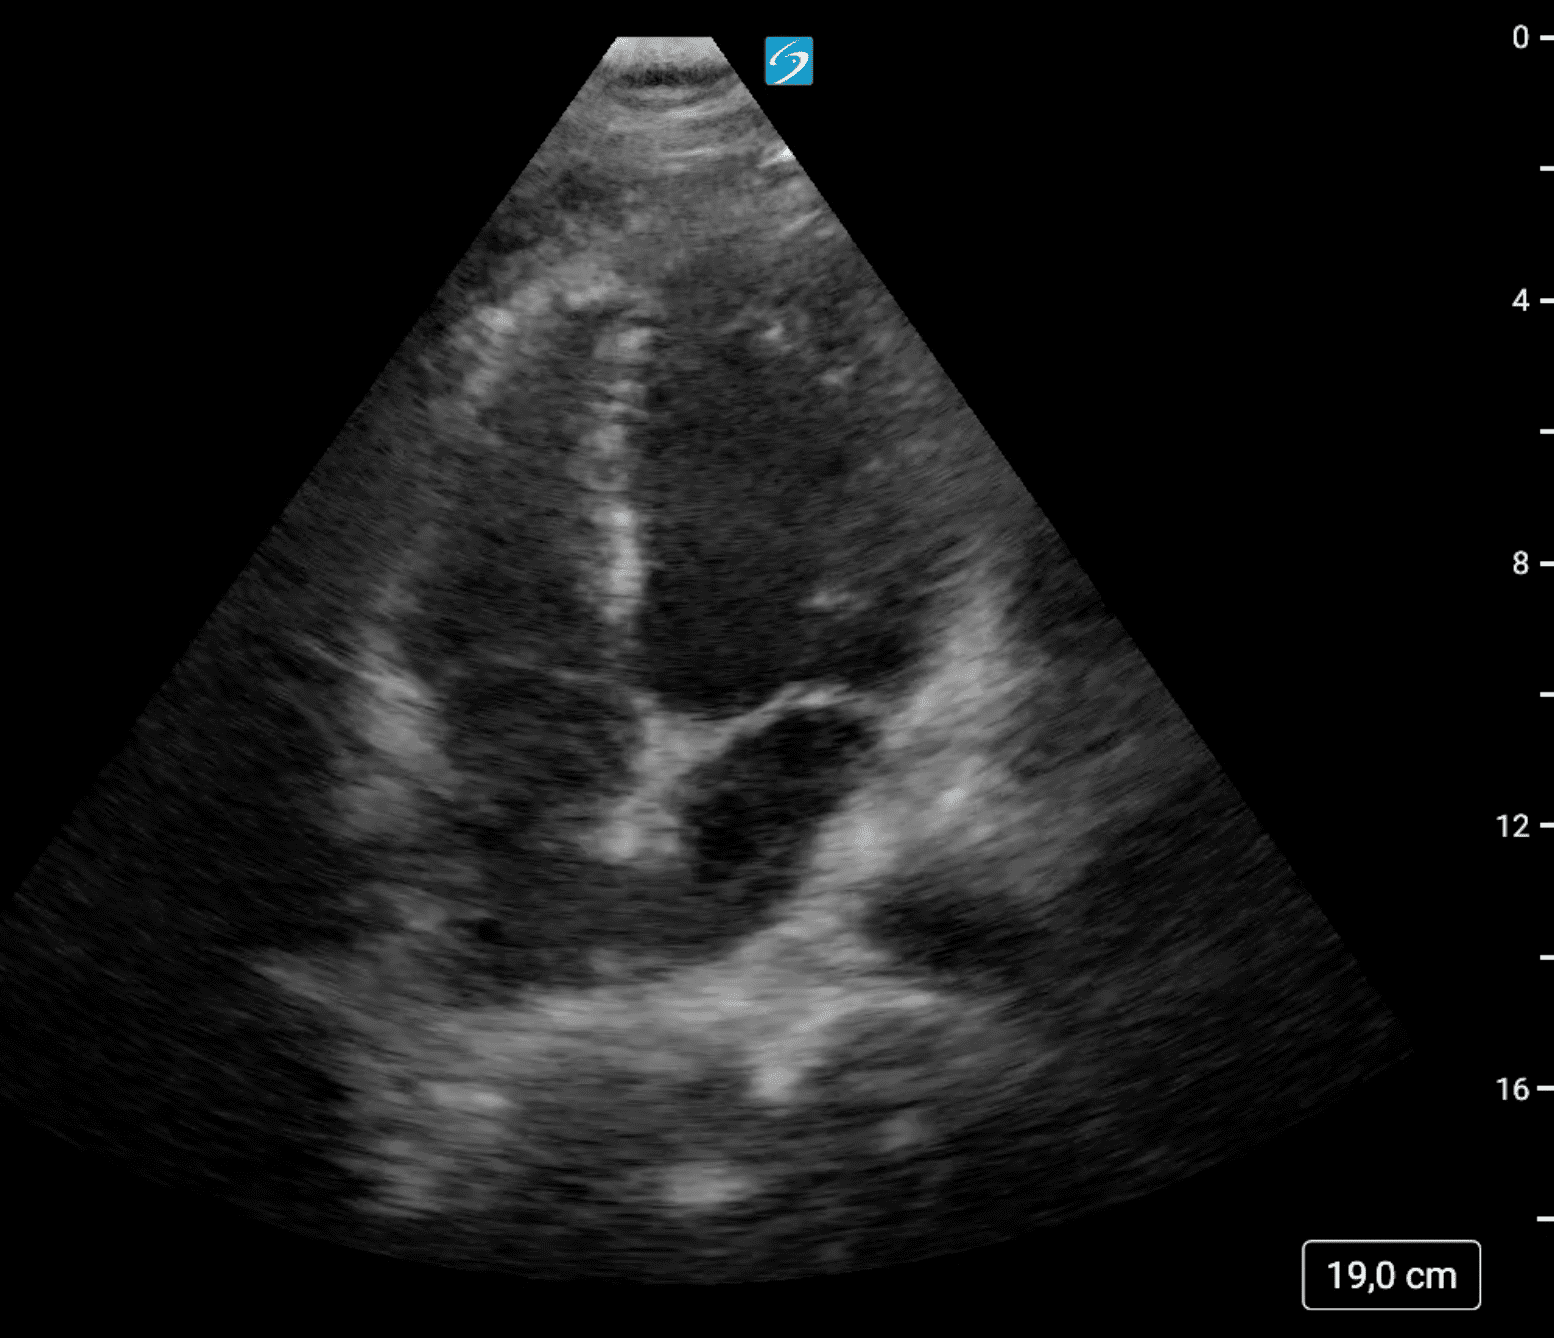

Se localiza ecográficamente la vena femoral común con una imagen hipoecogénica que no colapsa con a la compresión y que se extiende por femoral superficial hasta poplítea. Tras hallazgos, se realiza también una ecografía cardíaca, con un diámetro de visu VD/VI < 1 y con una función cardíaca conservada, con resultado en escala PESI de riesgo bajo.

Como diagnóstico diferencial se valoran celulitis e insuficiencia venosa crónica. Se realiza una ecografía reglada que confirma el diagnóstico de sospecha de trombosis venosa profunda (TVP) extensa subaguda.